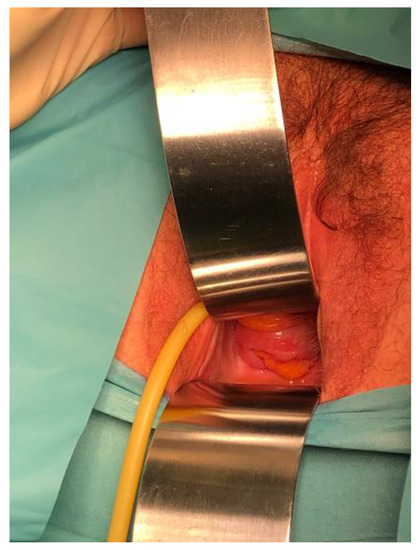

Objectives: The aim of this study is to demonstrate the efficacy of the modified technique of radical organ-preserving surgery of invasive cervical cancer (CC) in patients of reproductive age. Methods: This study included 118 patients of reproductive age (34.9 ± 4.8 [...] Read more.

Objectives: The aim of this study is to demonstrate the efficacy of the modified technique of radical organ-preserving surgery of invasive cervical cancer (CC) in patients of reproductive age. Methods: This study included 118 patients of reproductive age (34.9 ± 4.8 years) with a morphologically verified diagnosis of invasive CC (T1a-1bNxM0). All patients underwent organ-preserving surgery in the scope of radical trachelectomy. A shape memory mesh implant woven in the form of a stocking from superelastic nickelide titanium thread with subsequent fixation with separate sutures around the perimeter was used to form the uterine closure apparatus and to strengthen the utero-vaginal anastomosis. The mesh implant was made of superelastic thin nickelide titanium threads with a diameter of 60–40 microns on a metal knitting machine. All patients were prospectively followed up for a mean of 120 months. Results: No intraoperative or postoperative complications were revealed when using a shape memory implant made of titanium nickelide during radical trachelectomy to form a locking apparatus and strengthen the anastomosis zone. No cervical stenoses or mesh failures were noted in any case. The 5-year overall and recurrence-free survival rates were 100% and 98%, respectively. Two patients indicated recurrence; it occurred in 3 and 36 months. There were 42 spontaneous pregnancies, and 29 resulted in full-term delivery, whereas 2 and 11 ended in miscarriage and early abortion, respectively. Currently, 18 patients are at different stages of the use of assisted reproductive technologies. Conclusions: The shape memory implant made of titanium nickelide integrates well into the surrounding tissues and successfully imitates the effect of the cervix. The use of this sparing-surgery technique has shown reasonably good results in carrying the pregnancy to term and good reproductive outcomes. Full article

Show Figures

Figure 1